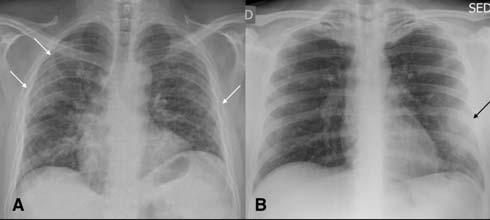

Fig 1 — CXR (A) and CT (B) images of a 45-year-old male who presented with fever and cough. He had hypoxia and leukopenia on examination and his nasal swab was positive for SARS COV-2. CXR shows bilateral blurred opacities with unclear vascular margins (white arrow) with corresponding ground glass changes in the CT (black arrows). Images reproduced with permission from Covid-19 Database of the SocietaItaliana di Radiologia Medica e Interventistica.

Fig 2 — CXR (A) and CT (B& C) images of a 50-year-old man with 6 days history of fever and dry cough. RT-PCR test was positive. CXR shows bilateral diffuse opacities, with a more opaque patch in the right lower zone (white arrow). The corresponding CT shows the true extent of the disease (black arrows). Images reproduced with permission from Covid-19 Database of the Fleischner Society.

Fig 3 — CXR images from two different patients with COVID-19 showing peripheral areas of consolidation bilaterally in A and unilaterally in B (arrows). Images reproduced with permission from Covid-19 Database of the Societa Italiana di Radiologia Medica e Interventistica.